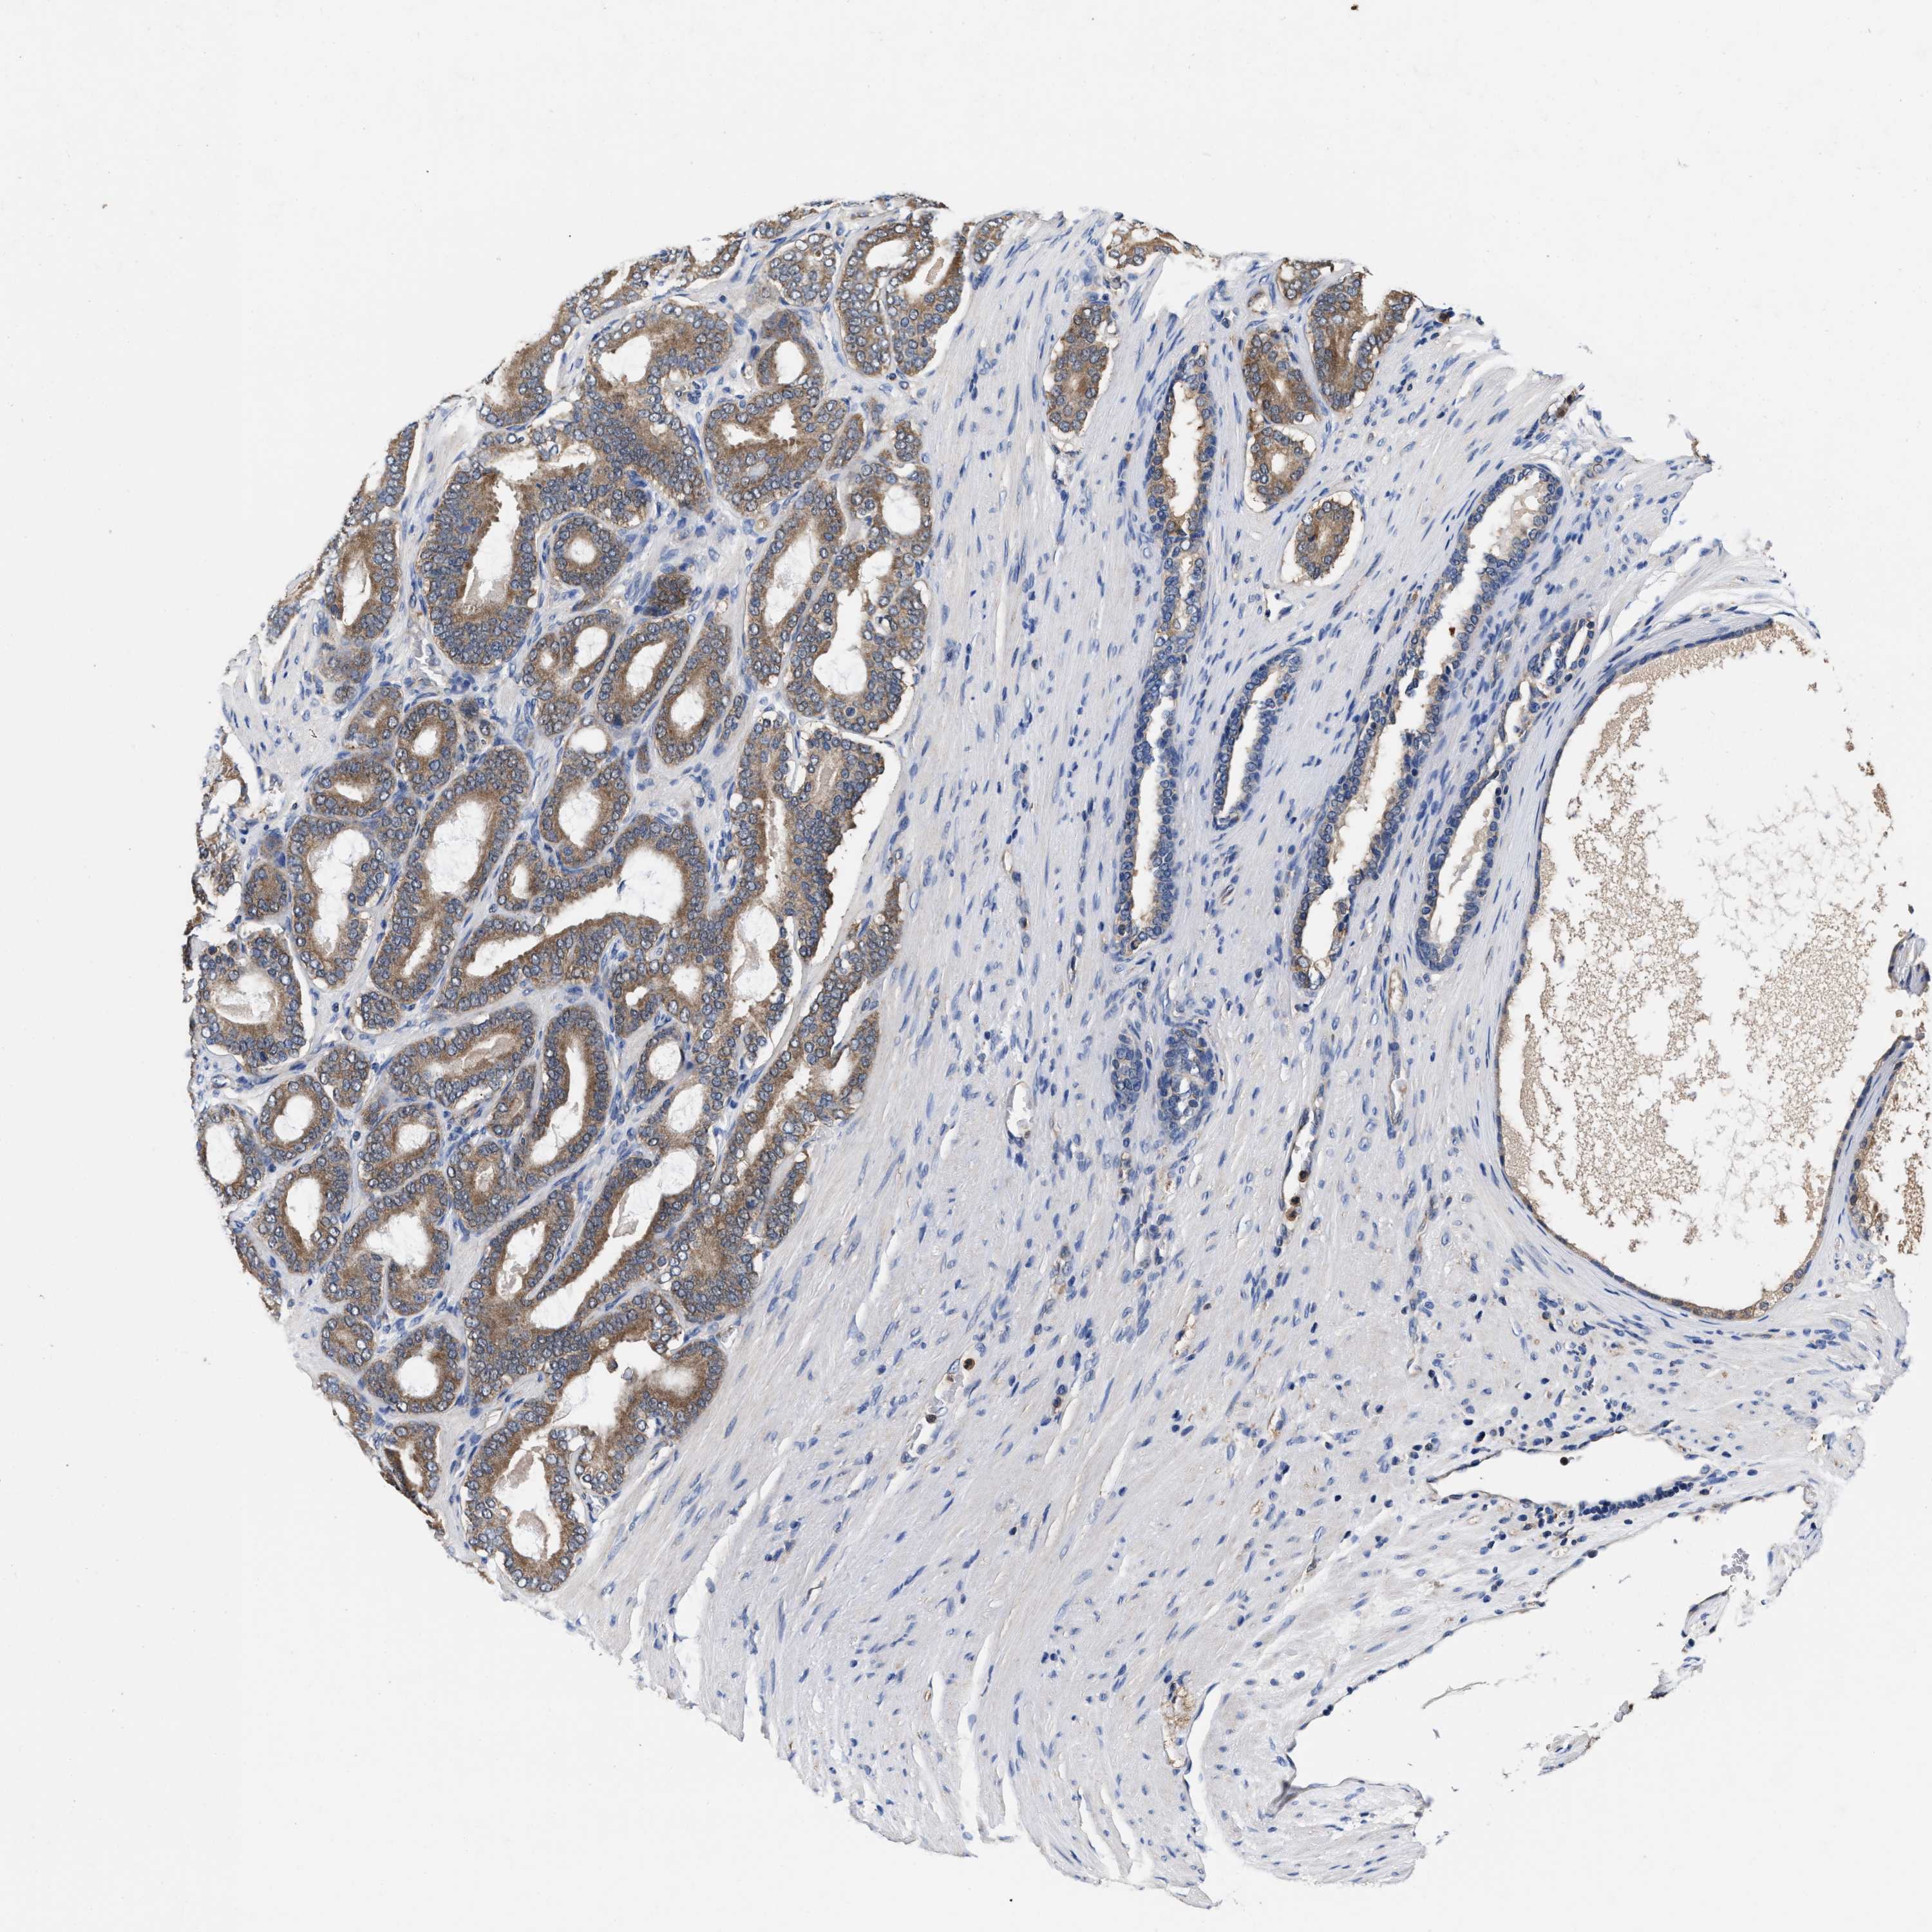

PROSTATE CANCER - Protein expressioni

A mouse-over function shows sample information and annotation data. Click on an image to view it in a full screen mode. Samples can be filtered based on level of antibody staining by selecting one or several of the following categories: high, medium, low and not detected. The assay and annotation is described here.

Antibody stainingi

Antibody staining in the annotated cell types in the current human tissue is reported as not detected, low, medium, or high, based on conventional immunohistochemistry profiling in selected tissues. This score is based on the combination of the staining intensity and fraction of stained cells.

Each image is clickable and will lead to virtual microscopy that enables deeper exploration of all samples and also displays staining intensity scores, fraction scores and subcellular localization as well as patient and tissue information for each sample.

HPA022434

HPA022953

HPA022959

HPA028758

CAB007783

Staining

High

Medium

Low

Not detected

Intensity

Strong

Moderate

Weak

Negative

Quantity

>75%

75%-25%

<25%

None

Location

Nuclear

Cytoplasmic/membranous

Cytoplasmic/membranous,nuclear

Adenocarcinoma, High grade

Adenocarcinoma, Low grade